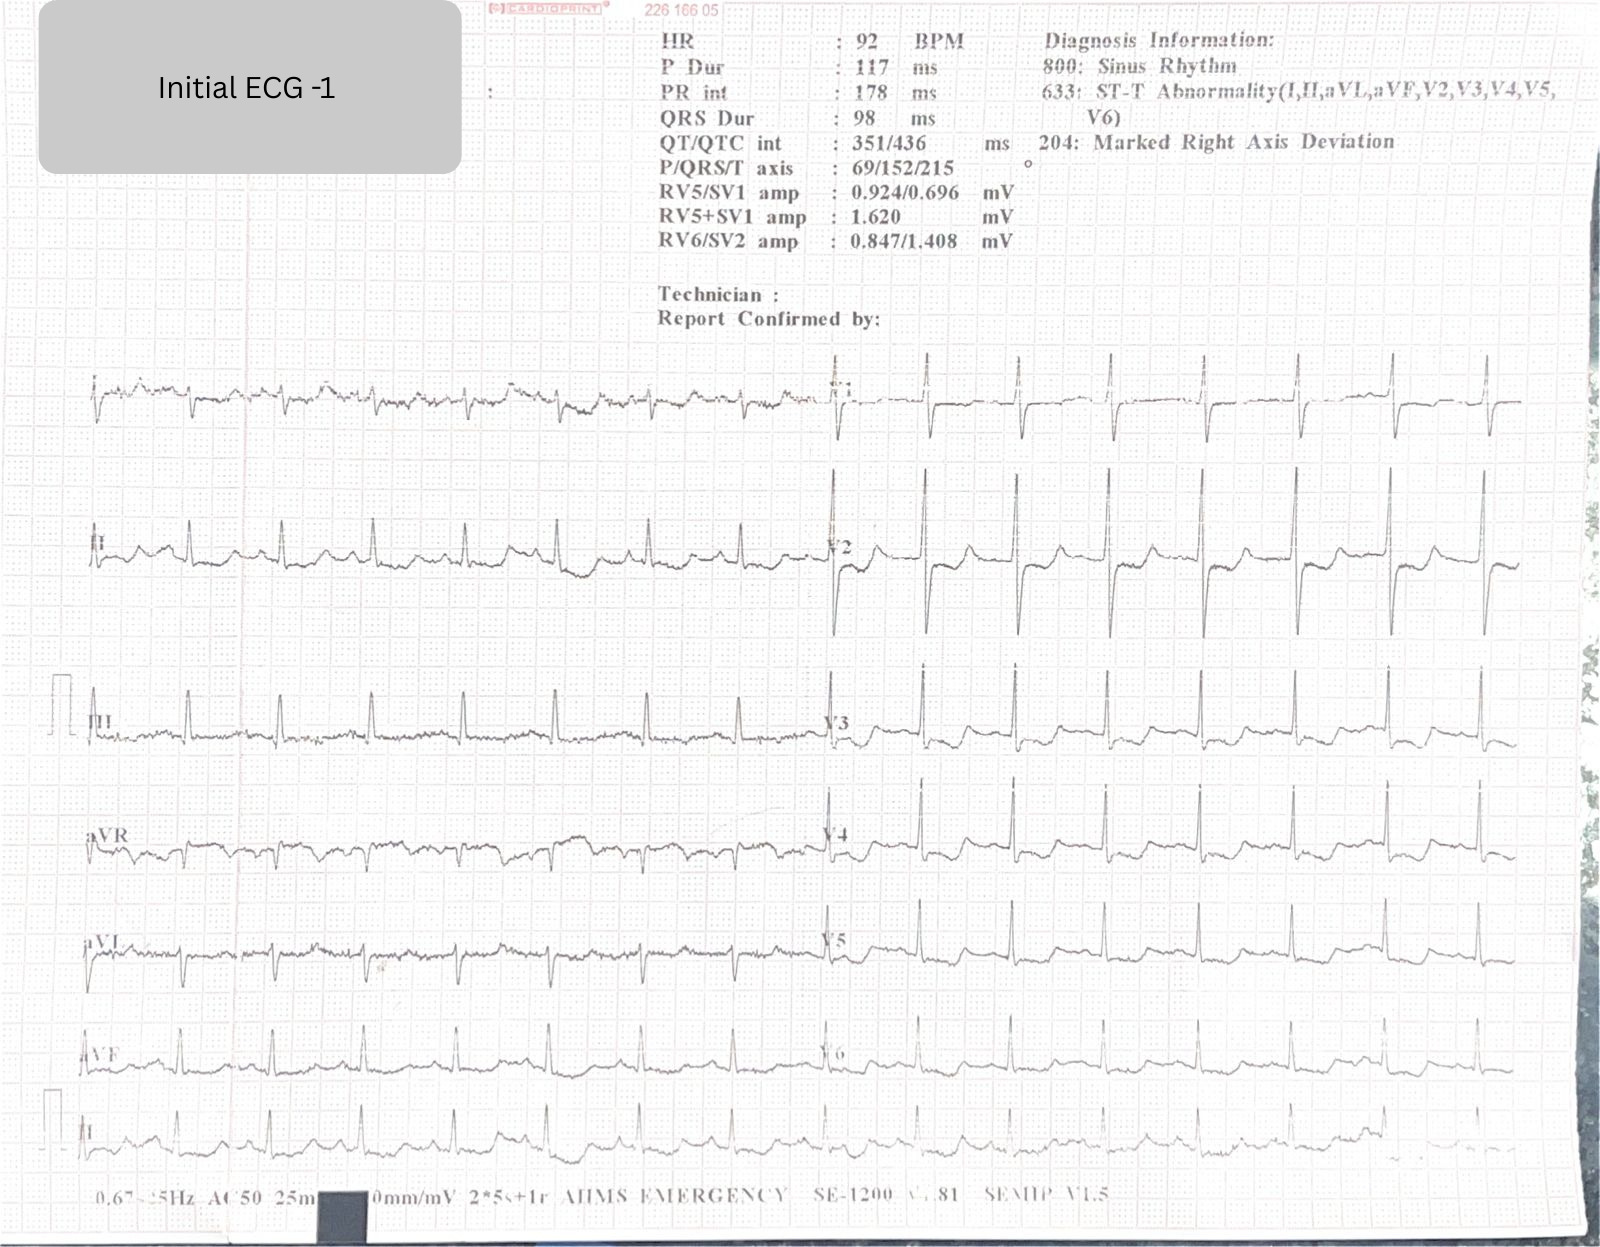

If you saw this ECG ,

aVR ST elevation.

V1 ST Segment elevated in comparison to V2.

Diffuse ST depression.

New right axis deviation.

your first instinct would probably be left main or proximal LAD occlusion.

ECG 1 was taken shortly after this massive blood loss.

ECG 1: The Concerning Findings

The initial ECG showed:

aVR ST elevation

V1 > V2 ST segment level

Diffuse ST depression

New right axis deviation (Lead I isoelectric/negative vs. ECG 2)

This pattern is alarming because it mimics:

Proximal LAD occlusion

Left main disease

Severe multivessel ischemia